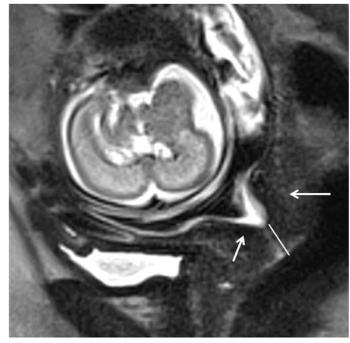

MRI helped predict which women with short cervix would go into preterm labor.

Case History: 25-year-old patient presents for fetal ultrasound.